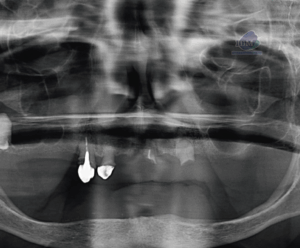

RECONSTRUCCIÓN 3D

La transmigración, es decir, la migración de dientes incluidos que traspasan la línea media, clásicamente se ha ceñido a caninos mandibulares, sin embargo, ya se han detectado casos de transmigración de caninos maxilares.

Muparappu y cols.2 en 2002, clasificó las transmigraciones en; Tipo I, cuando el canino se encuentra en posición mesio-angular a través de la sínfisis mandibular, con una disposición que puede ser vestibular o lingual con respecto a los dientes adyacentes pero siempre con la parte coronal cruzando la línea media; Tipo II, donde el canino se encuentra en posición horizontal cerca de la basal mentoniana por debajo de los ápices de los incisivos; Tipo III, aquellos caninos

transmigrados en erupción tanto si su posición es más mesial como más distal al canino contralateral; Tipo IV, la posición es horizontal cerca del reborde inferior de la rama mandibular, situándose por debajo de los premolares o molares de la hemiarcada contralateral; Tipo V, el canino se encuentra vertical respecto a la sínfisis mandibular, siendo el eje longitudinal el que cruza la línea media, independientemente del estado de erupción